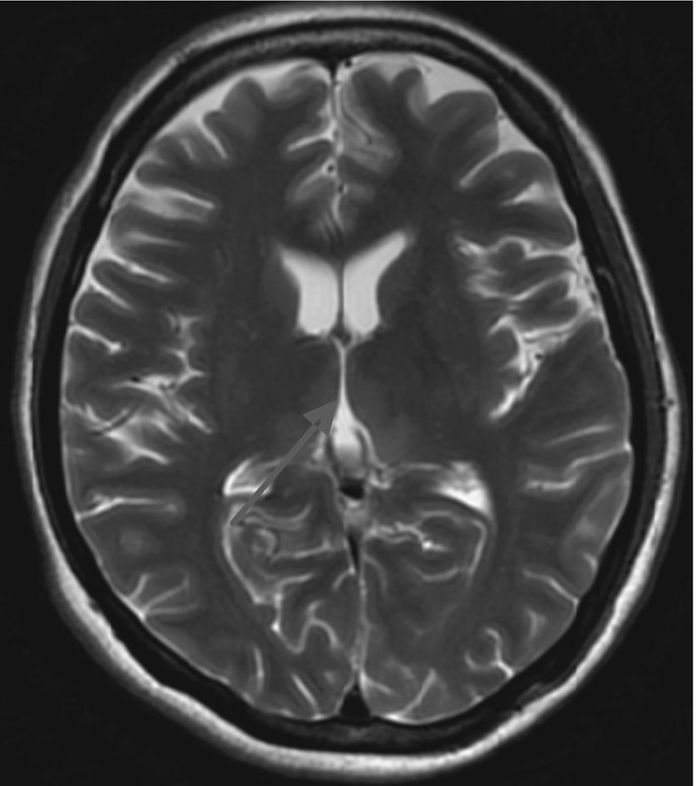

1 资料与方法患者女性,39岁,主因“复视1周,行走不稳4 d,意识障碍2 d”于2015年10月20日就诊北京大学人民医院急诊科。患者1周前出现复视,伴视物模糊、头晕,无头痛、恶心、呕吐。4 d前出现行走不稳,需家人搀扶,伴乏力。2 d前间断嗜睡,且意识障碍逐渐加重,后因呼之无反应,就诊当地医院行头颅CT示“脑桥可疑低密度灶”。既往:“慢性胰腺炎、慢性胆囊炎”3个月,进食差。否认药敏史。入院查体:T 37.8 ℃,HR 118次/min,RR 25次/min,BP 95/65 mmHg (1 mmHg=0.133 kPa),SpO2 90%。昏迷。双侧瞳孔等大等圆,直径3 mm,对光反射消失。双肺呼吸音粗,未闻及干湿性啰音。心率118次/min,律齐,心音较低,各瓣膜听诊区未闻及病理性杂音。腹软,肝脾肋下未触及。双下肢肌张力减低。病理征阴性。入我科后完善相关检查:血常规:WBC 6.28×109 L-1、Hb 104 g/L、PLT 279×109 L-1;生化全项:ALT 146 U/L、AST 81 U/L、ALB 40 g/L、GLU 6.87 mmol/L、TBIL 34.2 μmol/L、DBIL 15.3 μmol/L、Na+ 138 mmol/L、K+ 4.0 mmol/L、CRE 78 μmol/L;血气分析:pH 7.37,PaO2 168 mmHg (FiO2 29%),PaCO2 37 mmHg,SaO2 98%,Lac 2.7 mmol/L;头颅CT未见明显异常。初步诊断为意识障碍待查、肝功能损伤待查,予改善循环、营养神经、营养支持、护肝等治疗。考虑到患者院外饮食不佳近3个月,存在WE可能,予维生素B1 100 mg每日2次肌注。次日患者出现低氧血症,SpO2 78%~85%;血气分析:pH 7.36,PaO2 88 mmHg (FiO2 41%),PaCO2 30 mmHg,SaO2 83%,Lac 3.6 mmol/L;予气管插管接呼吸机辅助通气。10月28日脱机、拔除气管插管,予无创呼吸机序贯治疗。10月29日行头颅MRI示“双侧额叶皮层(图 1)、双侧丘脑、下丘脑、第三脑室、中脑导水管周围脑实质(图 2、图 3)异常信号影,符合Wernicke's脑病表现”,为进一步治疗收住院。入院后继续予营养神经、改善脑部血液循环、维生素B1 100 mg每日2次肌注等治疗。患者神志逐步恢复正常,可正常交流及缓慢行走,但表情淡漠、记忆力下降,复查肝功能正常,于2015年12月8日离院,门诊随访。

| 图 2 T2WI双侧丘脑、下丘脑、第三脑室、中脑导水管周围脑实质异常信号 |